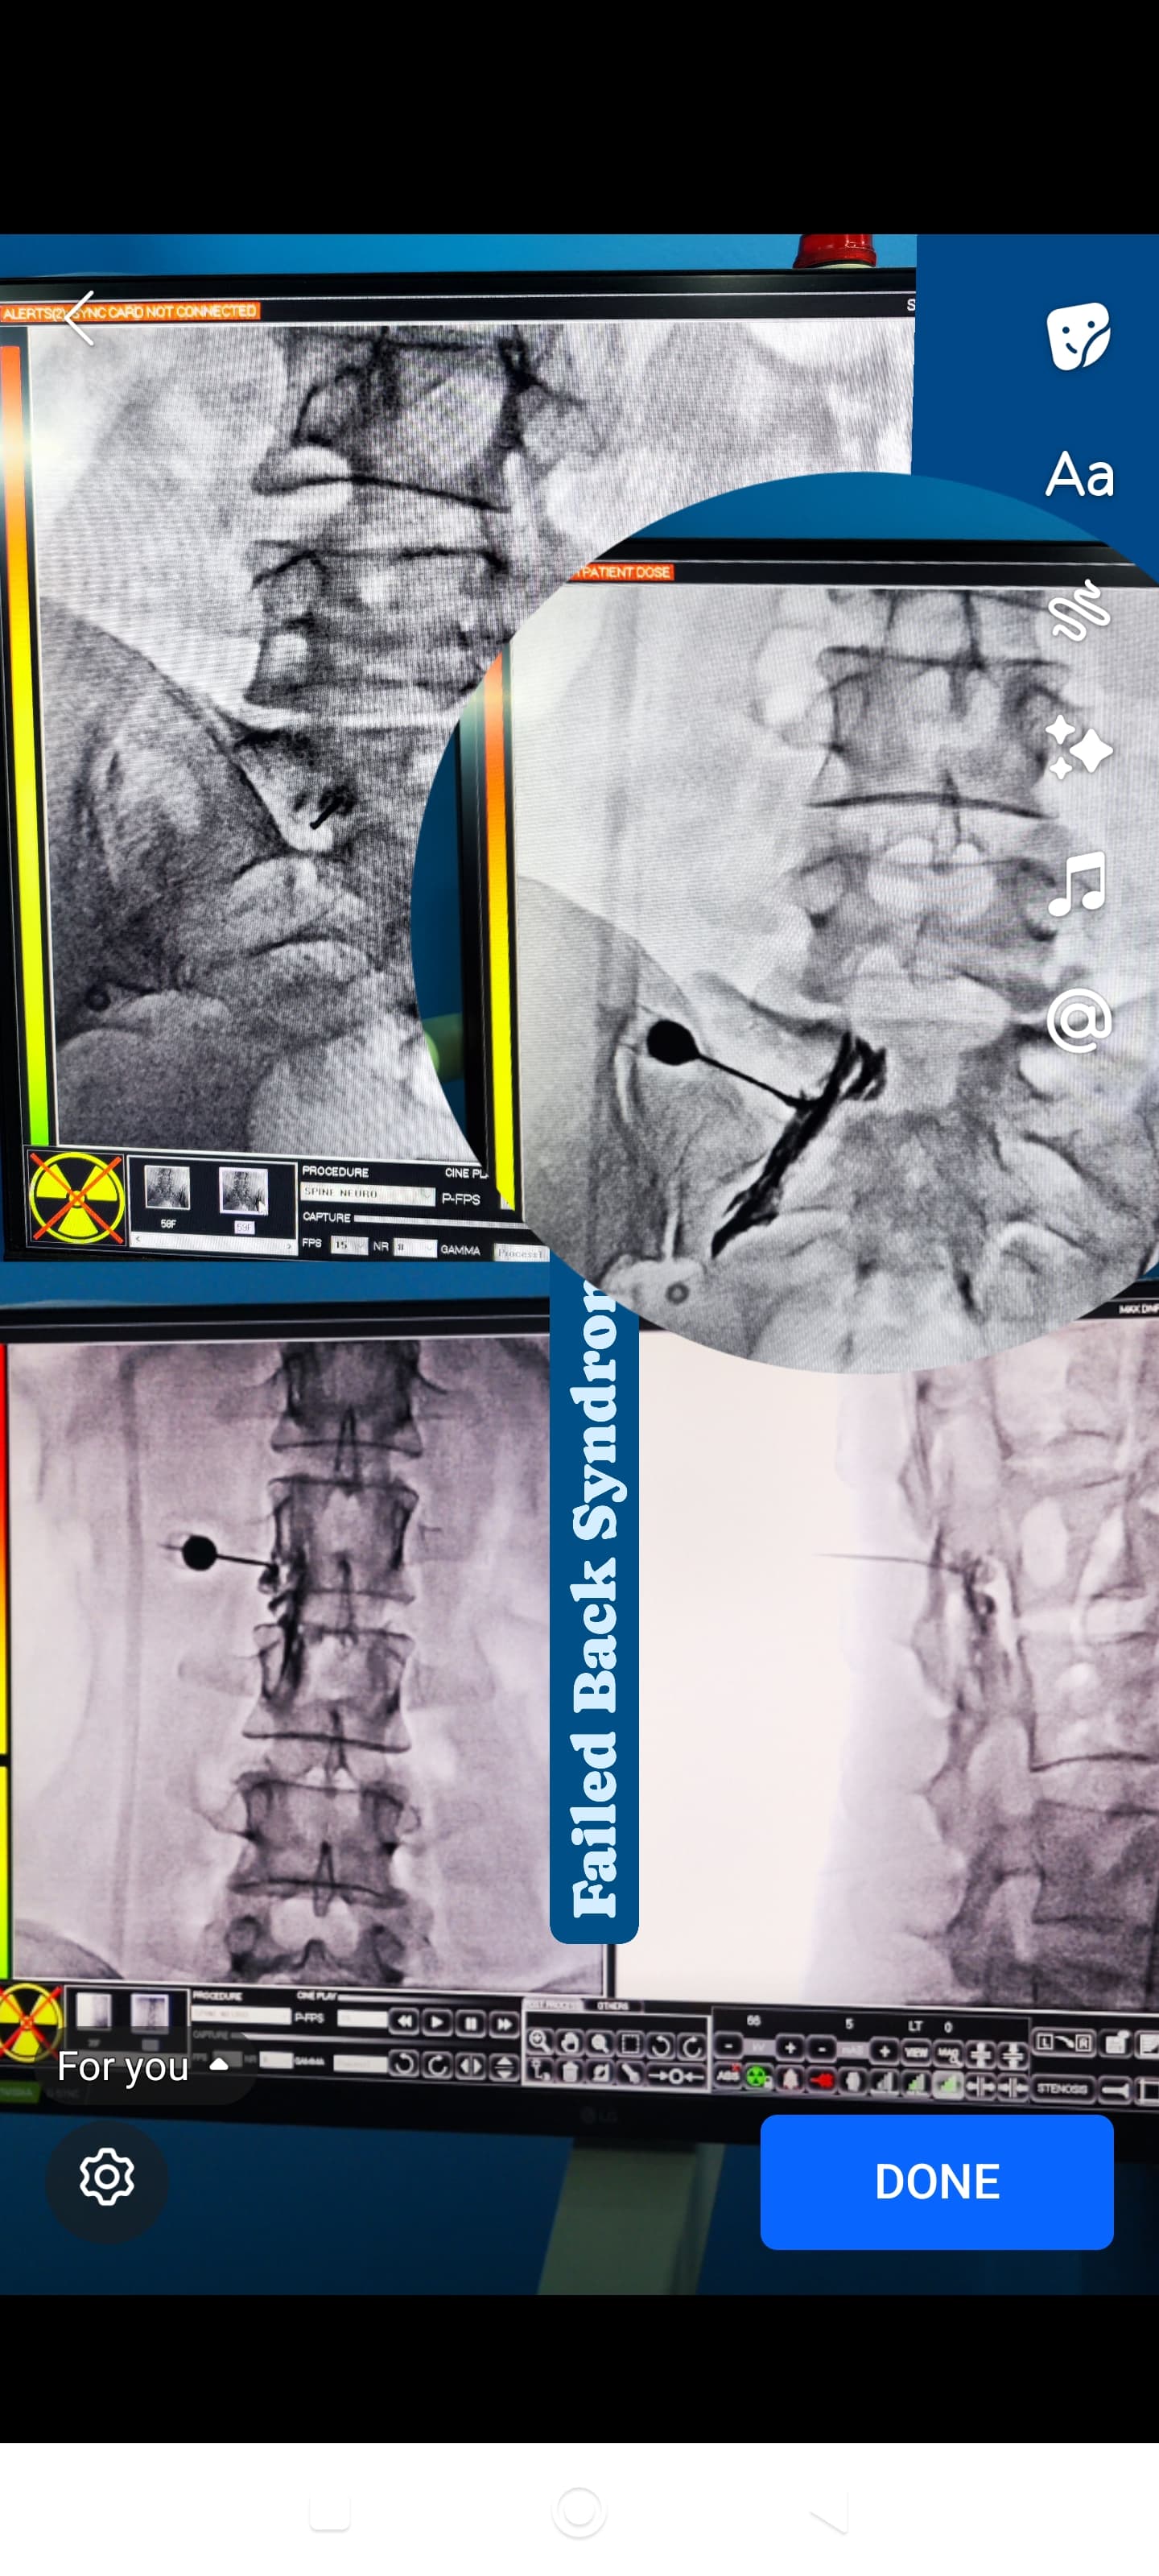

Epidural Injection helps ease back and leg pain by delivering medicine directly around the spine for quick, effective relief.

Intrathecal Pain Pump delivers medication directly to the spinal cord, providing powerful and long-term pain relief.

Radiofrequency Ablation Therapy reduces chronic pain by targeting specific nerves with heat for safe, lasting relief.

Neuromodulation Therapy manages chronic pain by regulating nerve signals, providing safe and effective long-term relief.